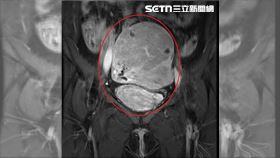

2寶媽患子宮肌腺經痛如刀割 醫靠1招解決

台中一名42歲蔡姓婦人,三年前生完二胎後,發現月經量...

像壁癌長不停!子宮肌腺症要切子宮?

子宮肌腺症就像「壁癌」一樣,多數長在子宮後壁,也有病...

輕熟女因這病子宮比正常大兩倍

39歲的凱莉(化名)長期飽受經痛與經血過多的困擾,不...